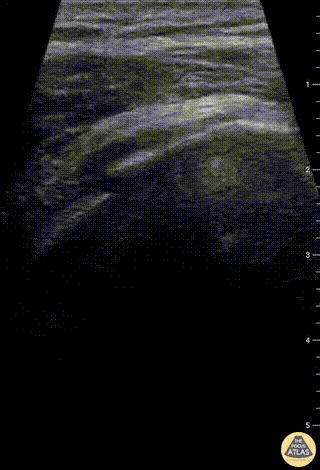

Musculoskeletal - Humeral Head fracture

Patient fell onto his left shoulder with point tenderness at the proximal humeral neck. Point-of-care ultrasound showed cortical break on a transverse view of the humeral head. Hyperechoic fluid was visualized in the glenohumeral joint, likely clotted blood. A comminuted humeral head/neck fracture was confirmed on XR. Charles Jang, EM PGY-3